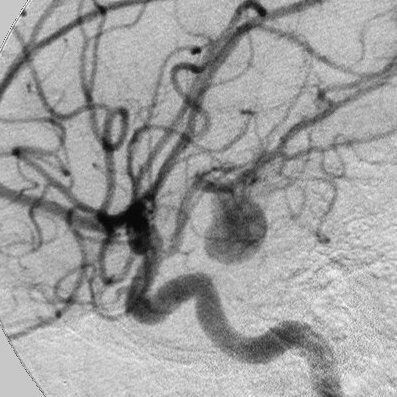

A Dios gracias, eso faltaba a la verdad. Cuando el cirujano doctor lo describió, me alegré. Un aneurisma es una falla congénita que puede suceder a cualquier edad. Es difícil de sanar, toma tiempo (mucho tiempo) y yo no contaba con ese preciado tesoro a mis 64 años.

No lo sabía aún, pero sufrí un hematoma subdural, en una de las tres capas que protegen el cerebro. No había caído en cuenta de un sangrado invisible crónico y nunca se me ocurrió pedir una resonancia.